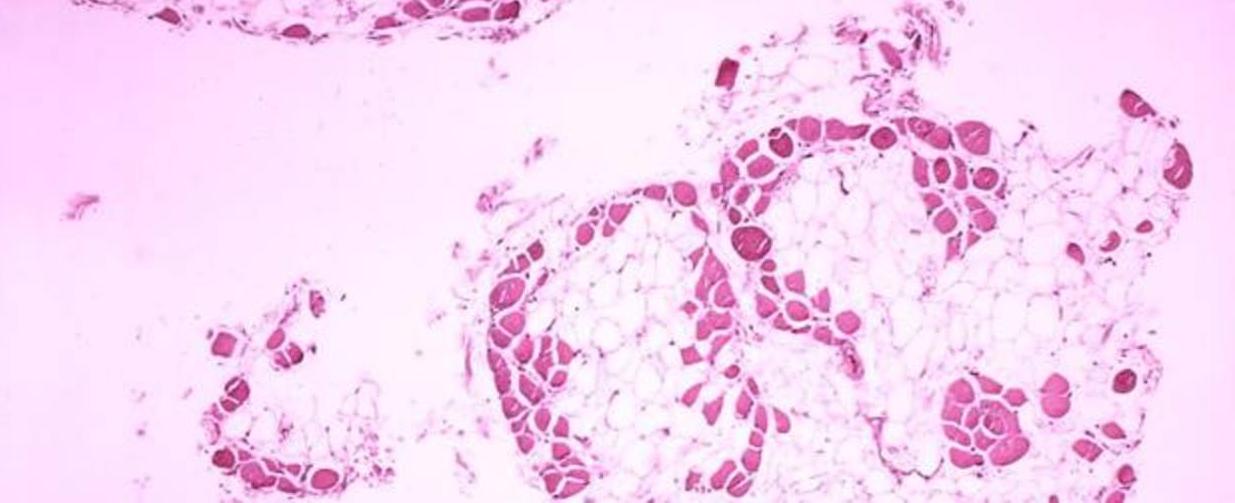

La distrofia muscular de Duchenne (DMD) es una enfermedad rara genética y degenerativa caracterizada por la ausencia de la distrofina, proteína responsable del buen funcionamiento de los músculos. En consecuencia, los afectados pierden ya durante la infancia la capacidad de caminar y, una vez alcanzada la adolescencia, la capacidad de utilizar sus brazos y de llevar a cabo actividades cotidianas –entre otras, alimentarse por sí mismos–. De ahí la importancia de la administración de glucocorticoides, fármacos que se vienen utilizando desde los años 80 en el tratamiento de la DMD al haber demostrado, entre otros beneficios, retrasar el deterioro de la fuerza y funcionalidad muscular a corto plazo. Pero, ¿qué ocurre a cuando se emplean estos glucocorticoides a largo plazo? Pues la verdad es que no se sabe. O así ha sido hasta ahora, dado que un estudio dirigido por investigadores de la Universidad de California en Davis (EE.UU.) ha demostrado, por primera vez, que el tratamiento a largo plazo con estos fármacos también induce beneficios en la DMD, incluida la conservación de la función y fuerza muscular y la reducción del riesgo de mortalidad.